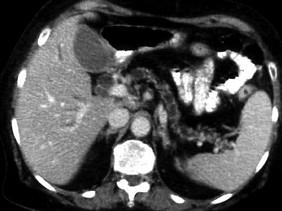

问题 胰头癌最主要的临床表现是 ( )

选项 A、消瘦和乏力 B、黄疸 C、食欲不振和消化不良 D、消化道梗阻 E、上腹疼痛 单选题

答案 B